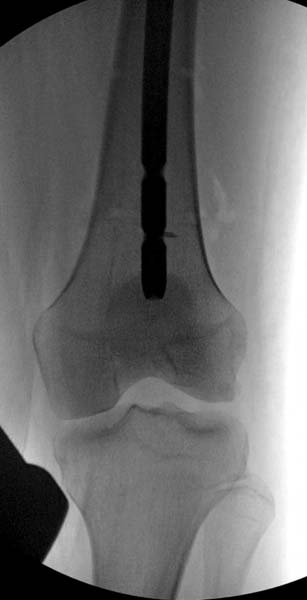

Около 11.00 вечера больная переведена в реанимацию, без сознания, но стабильная.. На третьий день провели стабилизацию перелома бедра антеградным остеосинтезом.

Закрытый БИОС решает множественные проблемы связанные с лечением переломов, но проблема дистальной блокировки без рентгена до сих пор остается нерешенной. Рекламированные производителями приспособления для дистальной блокировки из-за различной кривизны кости не эффективны или стоит очень дорого (Smith&Nephew SureLock). Задержка операции из-за блокировки не всегда удовлетворяет, и многих вынуждает искать альтернативные методы фиксации. С результатами таких действий, остеомиелитом и несращениями, встречаемся в ежедневной жизни..

Для решения проблемы дистальной блокировки компания DigiMed недавно предложила систему блокировки без рентгена. Пока в стране только два набора и только для антеградных гвоздей, но компания работает над созданием устроиства для других гвоздей тоже..

Результат первых случаев показала отсутствие разницы между занятиями на муляжах, а также Workshop и с удивительной точностью вывел латерально над кожей специальное сверло. Дальше по сверлу тонкий направитель и проводится сверление каннюлированным сверлом....